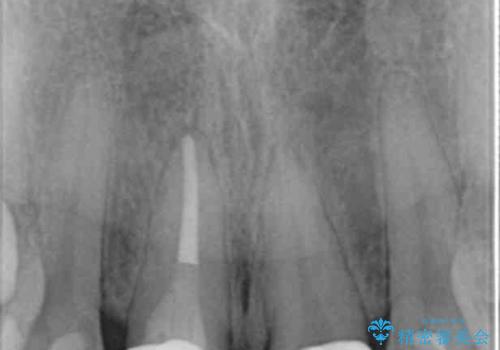

- 「 以前神経を取った歯の変色が気になる。前歯をきれいにして欲しい。」と治療を希望され来院されました。

目立つ上顎前歯に変色・大きな虫歯治療痕が見られ、審美障害を引き起こしています。

虫歯の徹底的な除去、根管治療を行いセラミック治療に入る前の環境をしっかりと整えたのち審美的なジルコニアセラミックで治療を仕上げました。